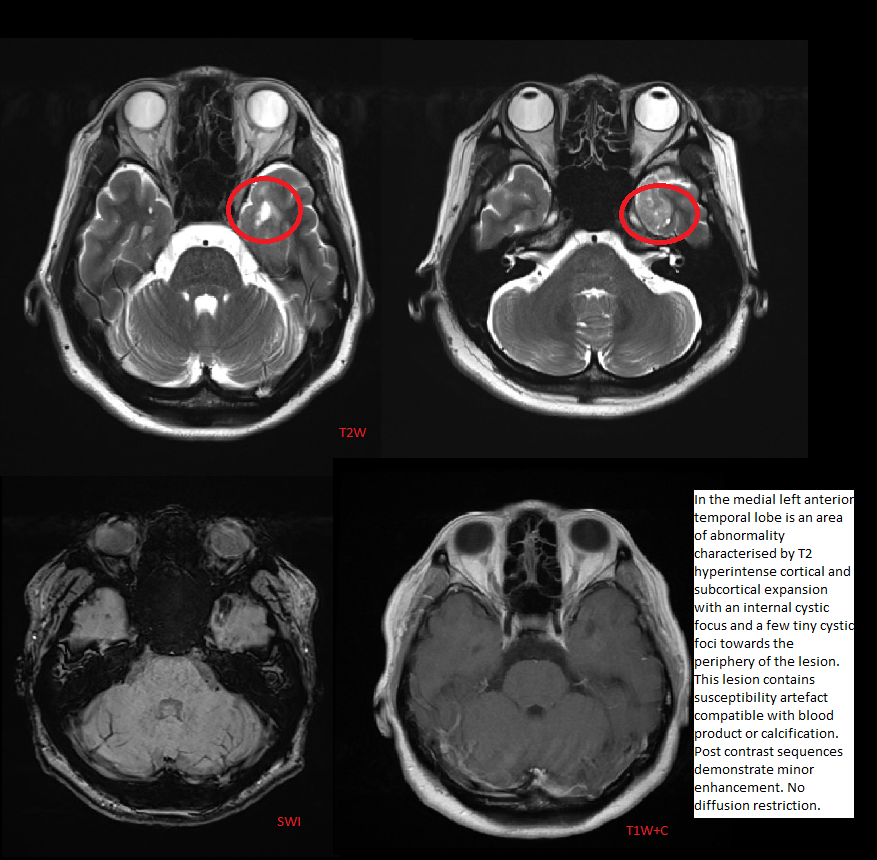

Imaging features of ganglioglioma

1. Most common neoplastic cause of temporal lobe seizures in adolescents/young adults.

2. Although its imaging appearance varies, the

most common presentation is a superficial mixed cystic and solid mass; the solid components often present as a mural nodule and are hyperintense on T2 sequences.

As the lesion is cortically based, cortical expansion and overlying bony remodeling is often seen.

CALCIFICATIONS and enhancement of

solid components are noted in approximately half of cases.

Meningeal enhancement and surrounding edema is mild,

when present.